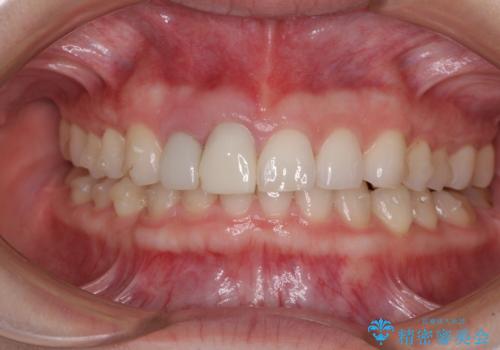

治療前、下顎前歯はほとんど見えない咬み合わせでしたが、矯正治療によりディープバイトが改善されました。

矯正治療中に前歯2本のクラウンは外れてしまい、途中仮歯に替える必要があったので期間は掛かりましたが、歯列も整い、負担のかからない咬み合わせを達成することができました。